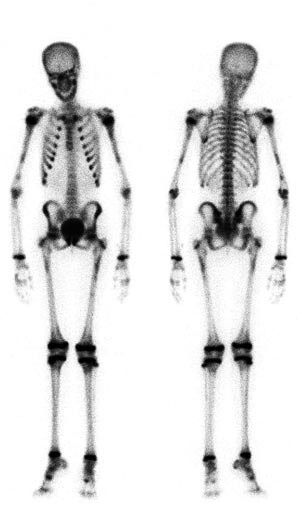

Pasient 4. Jente, ni år gammel, ble innlagt med smerter i nedre ribbbein på begge sider og mulig vekttap. Røntgen thorax viste oppfylling i øvre mediastinum. Skjelettscintigrafi viste i tillegg til generelt påfallende høyt skjelettopptak også fokalt økt aktivitet i flere områder i begge humerus- og femurdiafyser (fig 3). MR viste ødem i diafysene i begge humeri og i venstre femur. Det ble ikke tatt bronkialskylleprøve, men kun fastende ventrikkelaspirat som ikke gav vekst av M tuberculosis.

Skjelettscintigrafi med technetium-metylendifosfonat viser vanligvis økt aktivitetsoppladning med høy sensitivitet ved pyogene betennelser i beinvev (5) - (7, 14). Ved tuberkuløs osteomyelitt kan imidlertid metoden av og til svikte (7). Differensialdiagnoser som traumatisk skade og skjelettumor må has in mente (14). Redusert aktivitetsoppladning forenlig med nedsatt sirkulasjon pga. abscess eller nekrose, som hos pasient 2, er lett å overse. Skjelettscintigrafi kan imidlertid i en enkelt undersøkelse fremstille hele skjelettet og dermed avsløre flere (ev. uventede) patologiske foci, som hos pasient 4 (fig 3) hvor prosessen var kommet kort og symptomer og funn var beskjedne.